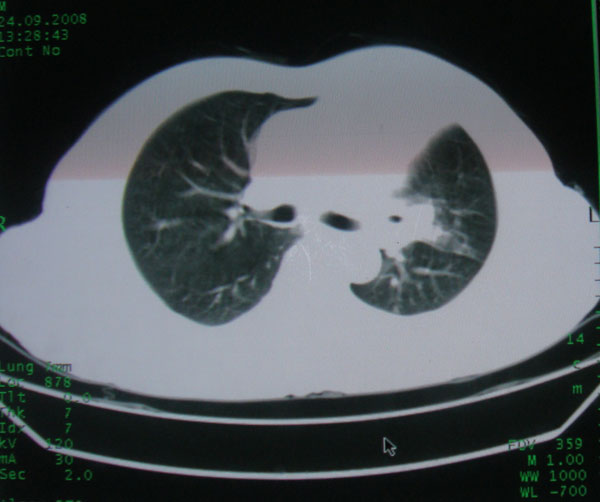

患者男性58岁因二周前起咳嗽,今天胸片示左上肺占位性病变行ct检查,无发热,无咯血痰.

左上肺感染性病变,结核伴空洞形成可能,左上肺膨胀不全

左肺上叶病灶,实变但见含气支气管、空洞但未见壁内结节及积液;

考虑:①感染性病变(包括特殊感染型肺tb)

②肿瘤性病变(考虑患者年龄比较大的关系/所以不排除)

初学者。。。左肺空洞性病变,并可见阻塞性肺不张改变,鉴于患者为老年男性,且临床症状仅有咳嗽,全身中毒症状不明显,所以我首先考虑为左肺癌性空洞并左侧肺门淋巴结转移伴左肺阻塞性肺不张。结核性空洞放于第二位考虑,可以进行相关实验室检查。希望能有病理结果,谢谢!!!!!

左肺上叶实变影,内见支气管充气征及空洞影,病人年龄较大,无发热及结核中毒症状,心影左移,未见纵隔淋巴结肿大;不知实验室检查结果如何?有否嗜酸细胞增多,有没有进行治疗?就目前资料首先考虑1.感染性病变,2.慢性嗜酸性肺炎?可结合实验室检查并短期治疗复查,肺癌不能排除。